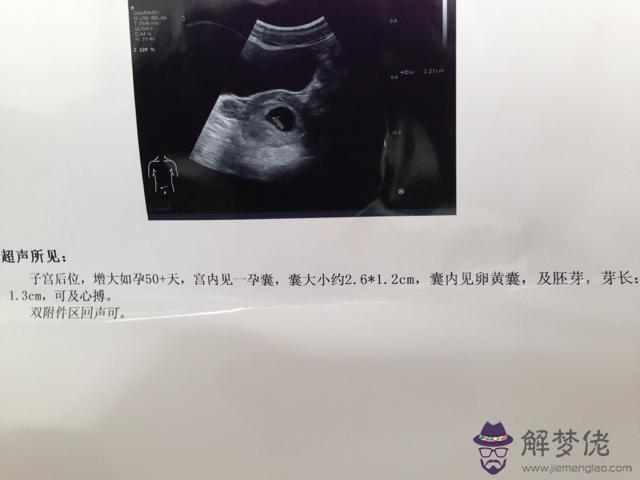

2、懷孕多久可以看出性別:幫忙看看四維單子是男是女謝謝

你好,看四維B超檢查報告,但是不能確定男孩女孩的這個準確性太差了,沒有什麼科學道理。

3、懷孕多久可以看出性別:四維單子可以看出男孩女孩嗎?

你好,根據這個四維彩色超聲檢查結果,是不能確定男孩女孩的,沒有什麼準確性。